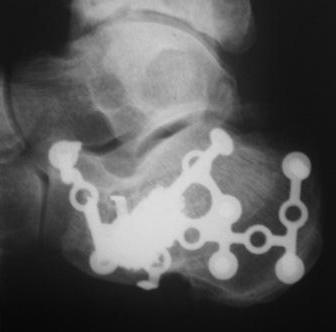

В качестве примера у себя нашёл снимки больного оперированного около двух лет назад, функция восстановлена полностью, ходит без каких бы то нибыло нарушений, сварщик - работает в полном объёме. Не сохранился первичный снимок, можете поверить на слово перелом примерно аналогичный, как у Вашего пациента.